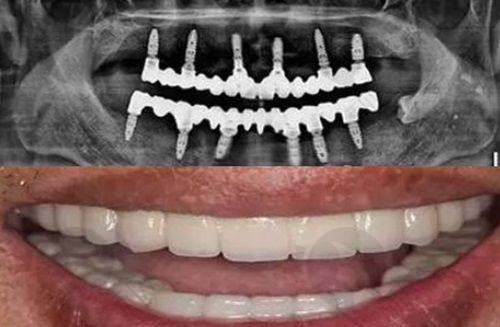

医院开展的项目齐全,涵盖了多个领域。种植牙是重点科室,开展即刻种植、微创种植、All - on - 4/6全口种植等高难度技术,合作进口品牌如瑞典诺贝尔、瑞士ITI等,特邀中韩医生团队联合诊疗,尤其擅长骨量不足患者的种植修复。牙齿矫正提供金属托槽矫正、隐形矫正(隐适美/时代天使)、舌侧矫正等,数字化模拟矫正结果,更准定制方案,儿童早期干预矫治(MRC肌功能训练)也备受家长好评。美学修复包括超薄瓷贴面、全瓷牙冠、牙齿美白(冷光/皓齿美白),注重自然美学设计,打造明星同款笑容。牙周治疗与儿童齿科开展激光牙周治疗、儿童防龋涂氟、窝沟封闭、舒适拔牙等,配备儿童专属诊室和趣味动画播放,缓解孩子看牙恐惧。

在设备方面,医院采用数字化诊疗设备,如德国西诺德CBCT、3D口扫仪等,确保更准诊疗。还依托五评级酒店环境,配备舒适麻醉仪等设备,诊疗更准舒适。采用CAD/CAM数字化修复系统,实现当天取牙冠,动态空气消毒技术,确保无菌环境。